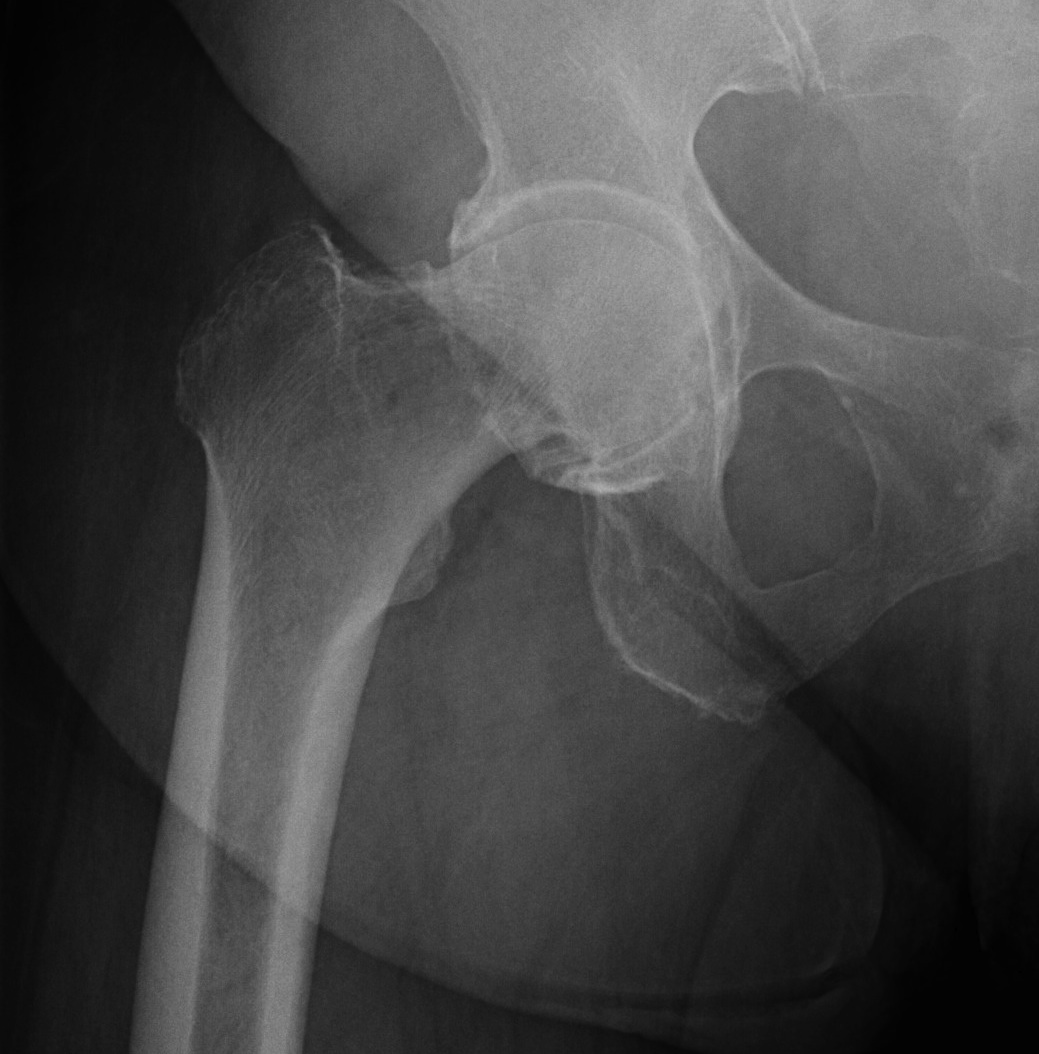

Etiology

Primary OA: 50%

Secondary OA: 50%

Secondary OA

FAI